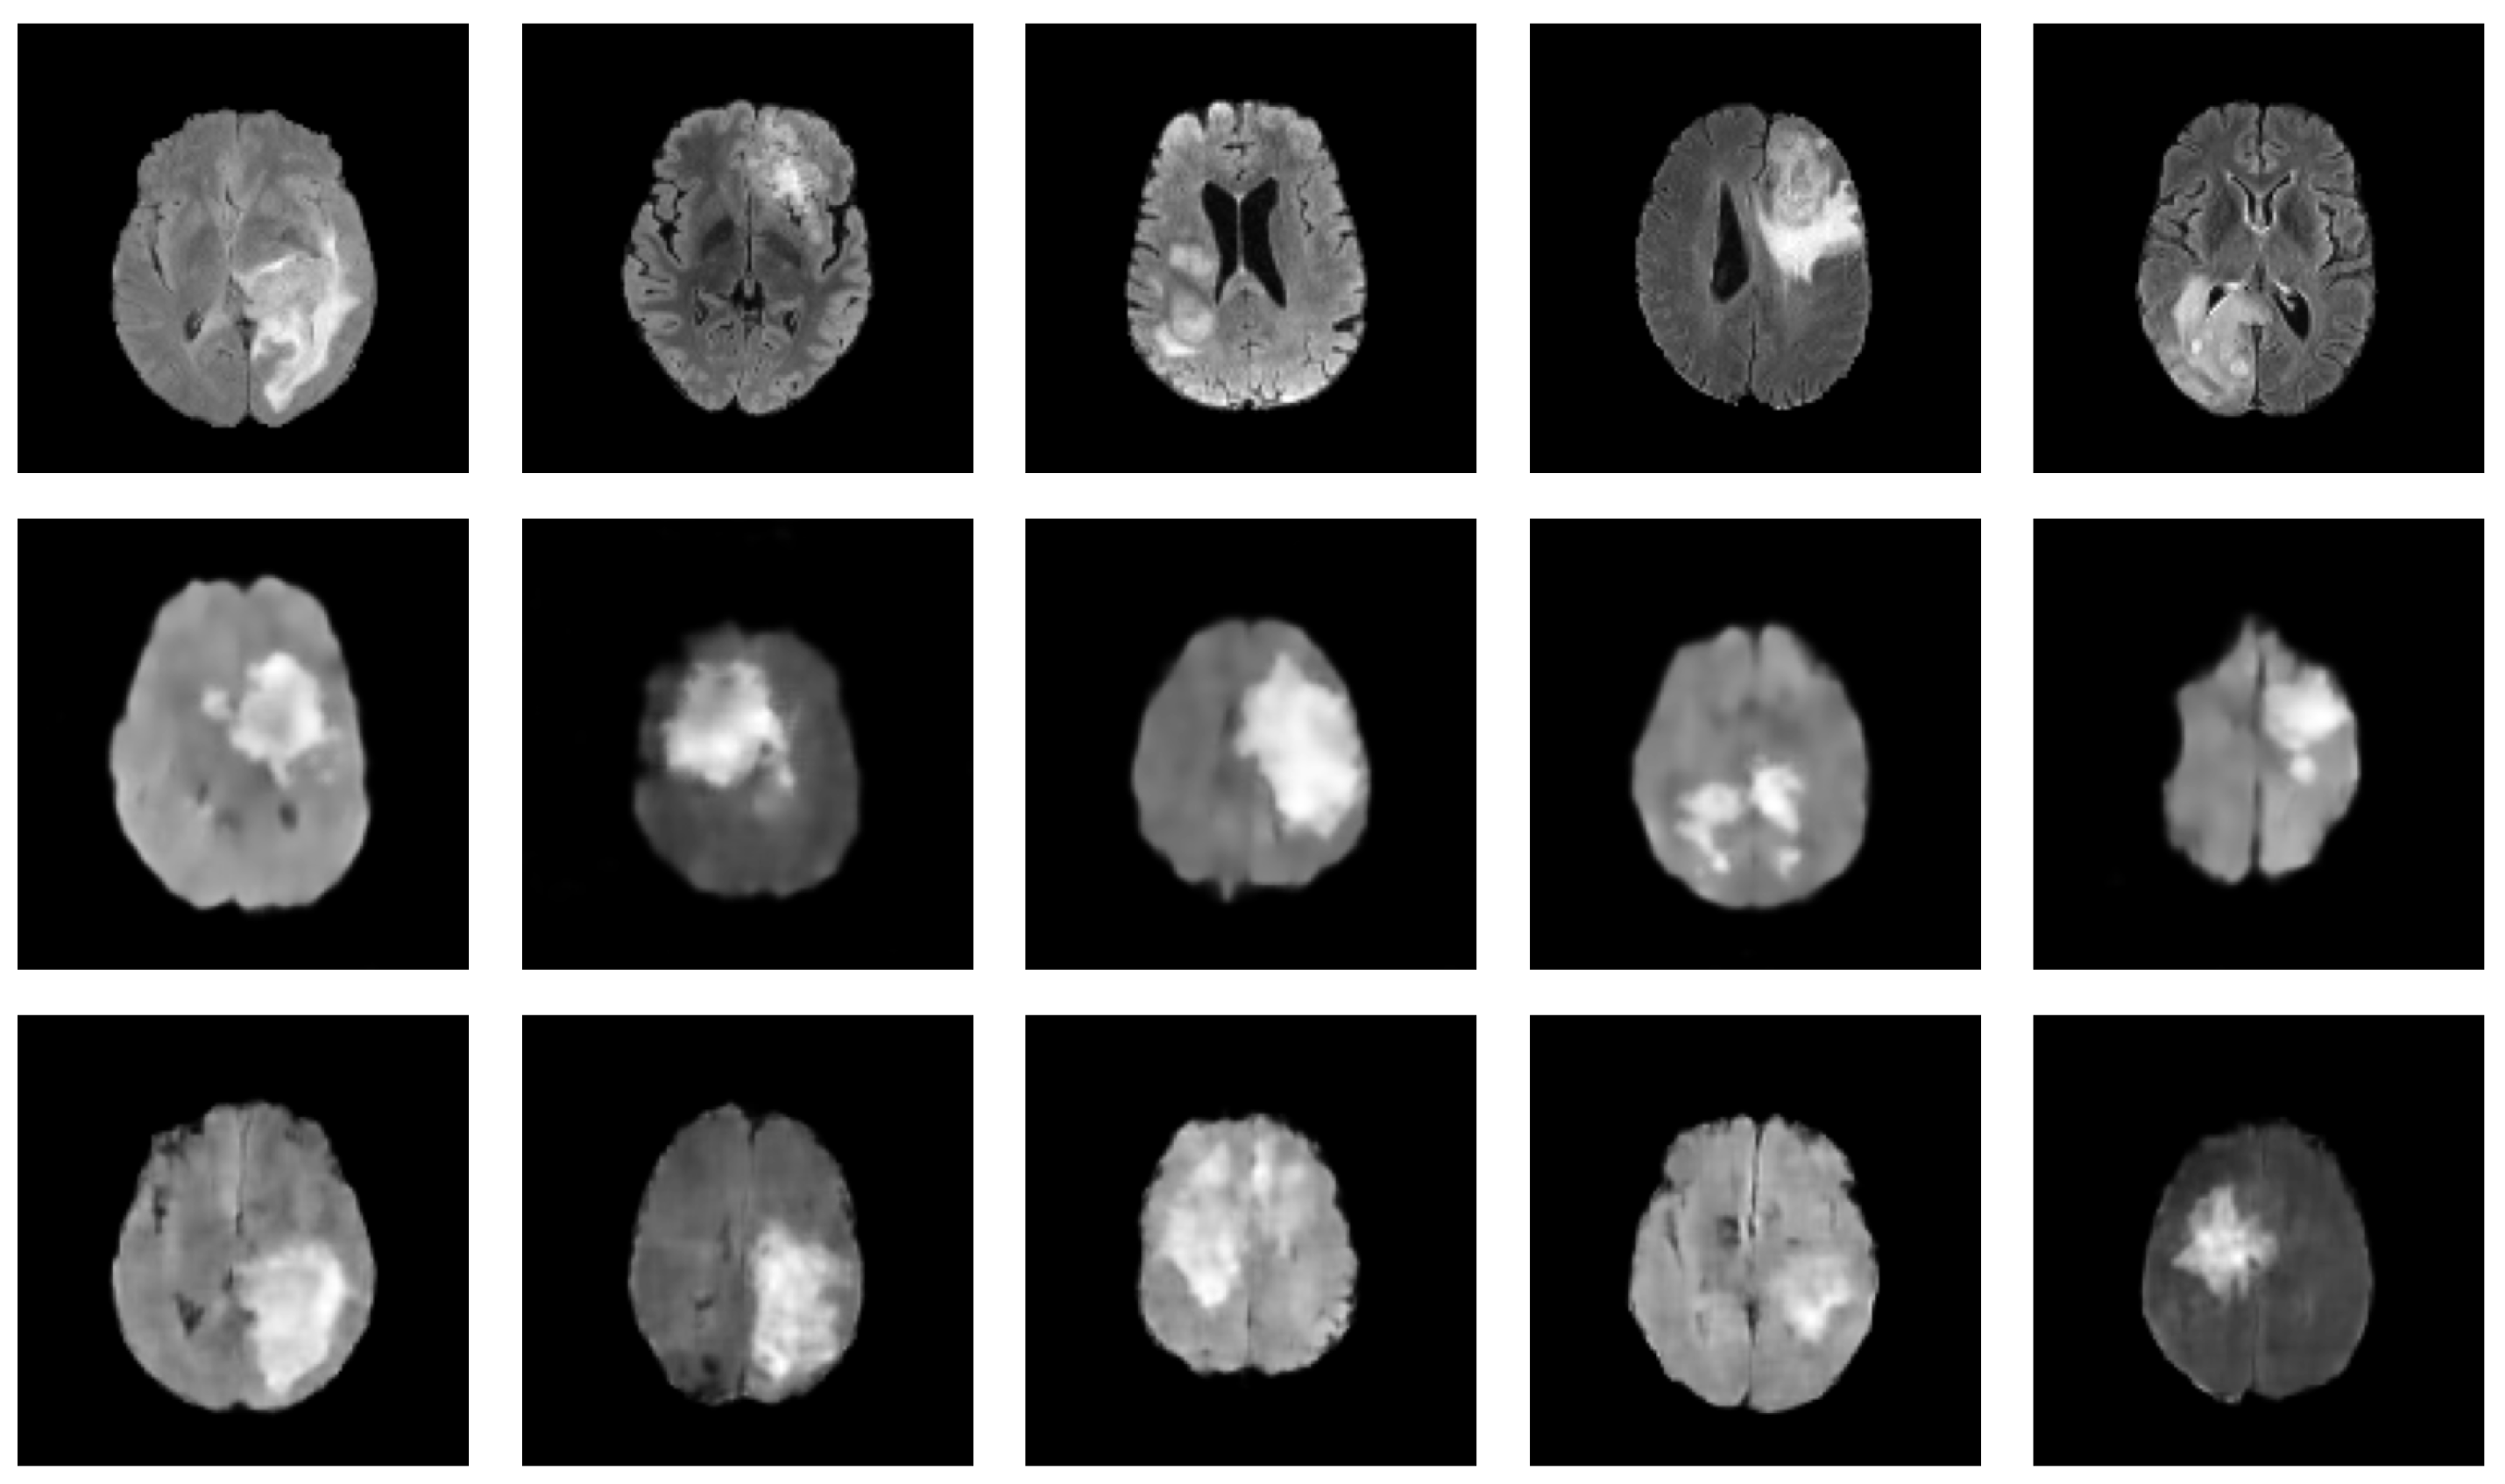

Table 3 presents a summary of the relevant studies utilizing diffusion models for medical image augmentation. These studies, all of which are relatively recent, with the earliest dating back to 2022, suggest that diffusion models have gained increasing attention in medical image augmentation and synthesis in recent years. Furthermore, in 2022, diffusion models have been the most-commonly used generative models for medical image augmentation compared to GANs and VAEs, highlighting their growing popularity and potential for use in various scenarios. Of the diffusion models studied, DDPM and LDM are the most prevalent, alongside conditional variants such as CDDPM [103] and CLDM [97]. Notably, the difference between LDM and DDPM is the ability of LDM to model long-range dependencies within the data by constructing a low-dimensional latent representation and diffusing it, while DDPMs apply the diffusion process directly to the input images. This can be especially useful for medical image augmentation tasks that require capturing complex patterns and structures. For instance, Saeed et al. [114] demonstrated the capacity of LDM conditioned on text for a task of lesion identification, achieving an accuracy improvement of 5.8%. These findings suggest that diffusion models have a promising potential for future medical image augmentation and synthesis research. To further exemplify the potential of diffusion models in generating realistic medical images, we present in Figure 4 a set of synthesized MRI images using a DDPM. These generated images exhibit high visual fidelity and are almost indistinguishable from the real images. One of the reasons for this high quality is the DDPM’s ability to model the diffusion process of the image density function. By doing so, the DDPM can generate images with increased sharpness and fine details, as seen in the synthesized MRI images.

Figure 4.

Synthesized MRIs using a diffusion-based probabilistic model (DDPM) [20] trained on the BraTS2020 dataset. The first row shows a sample of original images, while the second row shows a sample of synthesized images generated using the DDPM.